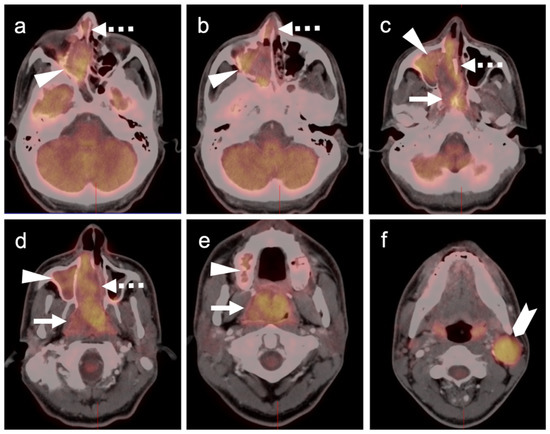

- Goerres, G.W.; Stoeckli, S.J.; Von Schulthess, G.K.; Steinert, H.C. FDG PET for Mucosal Malignant Melanoma of the Head and Neck. Laryngoscope 2002, 112, 381–385. [Google Scholar] [CrossRef]

- Murphy, G.; Hussey, D.; Metser, U. Non-cutaneous melanoma: Is there a role for18F-FDG PET-CT? Br. J. Radiol. 2014, 87, 20140324. [Google Scholar] [CrossRef] [Green Version]